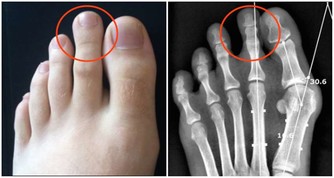

腮腺是人體唾液腺中最大的腺體,位於人面部兩側臉頰近耳垂處。正常人群中腮腺並不明顯,

當受到感染時,由於局部炎症導致的紅腫熱痛,

能明顯的看到以耳垂為中心發展而來的腫大,多數以單側多發。